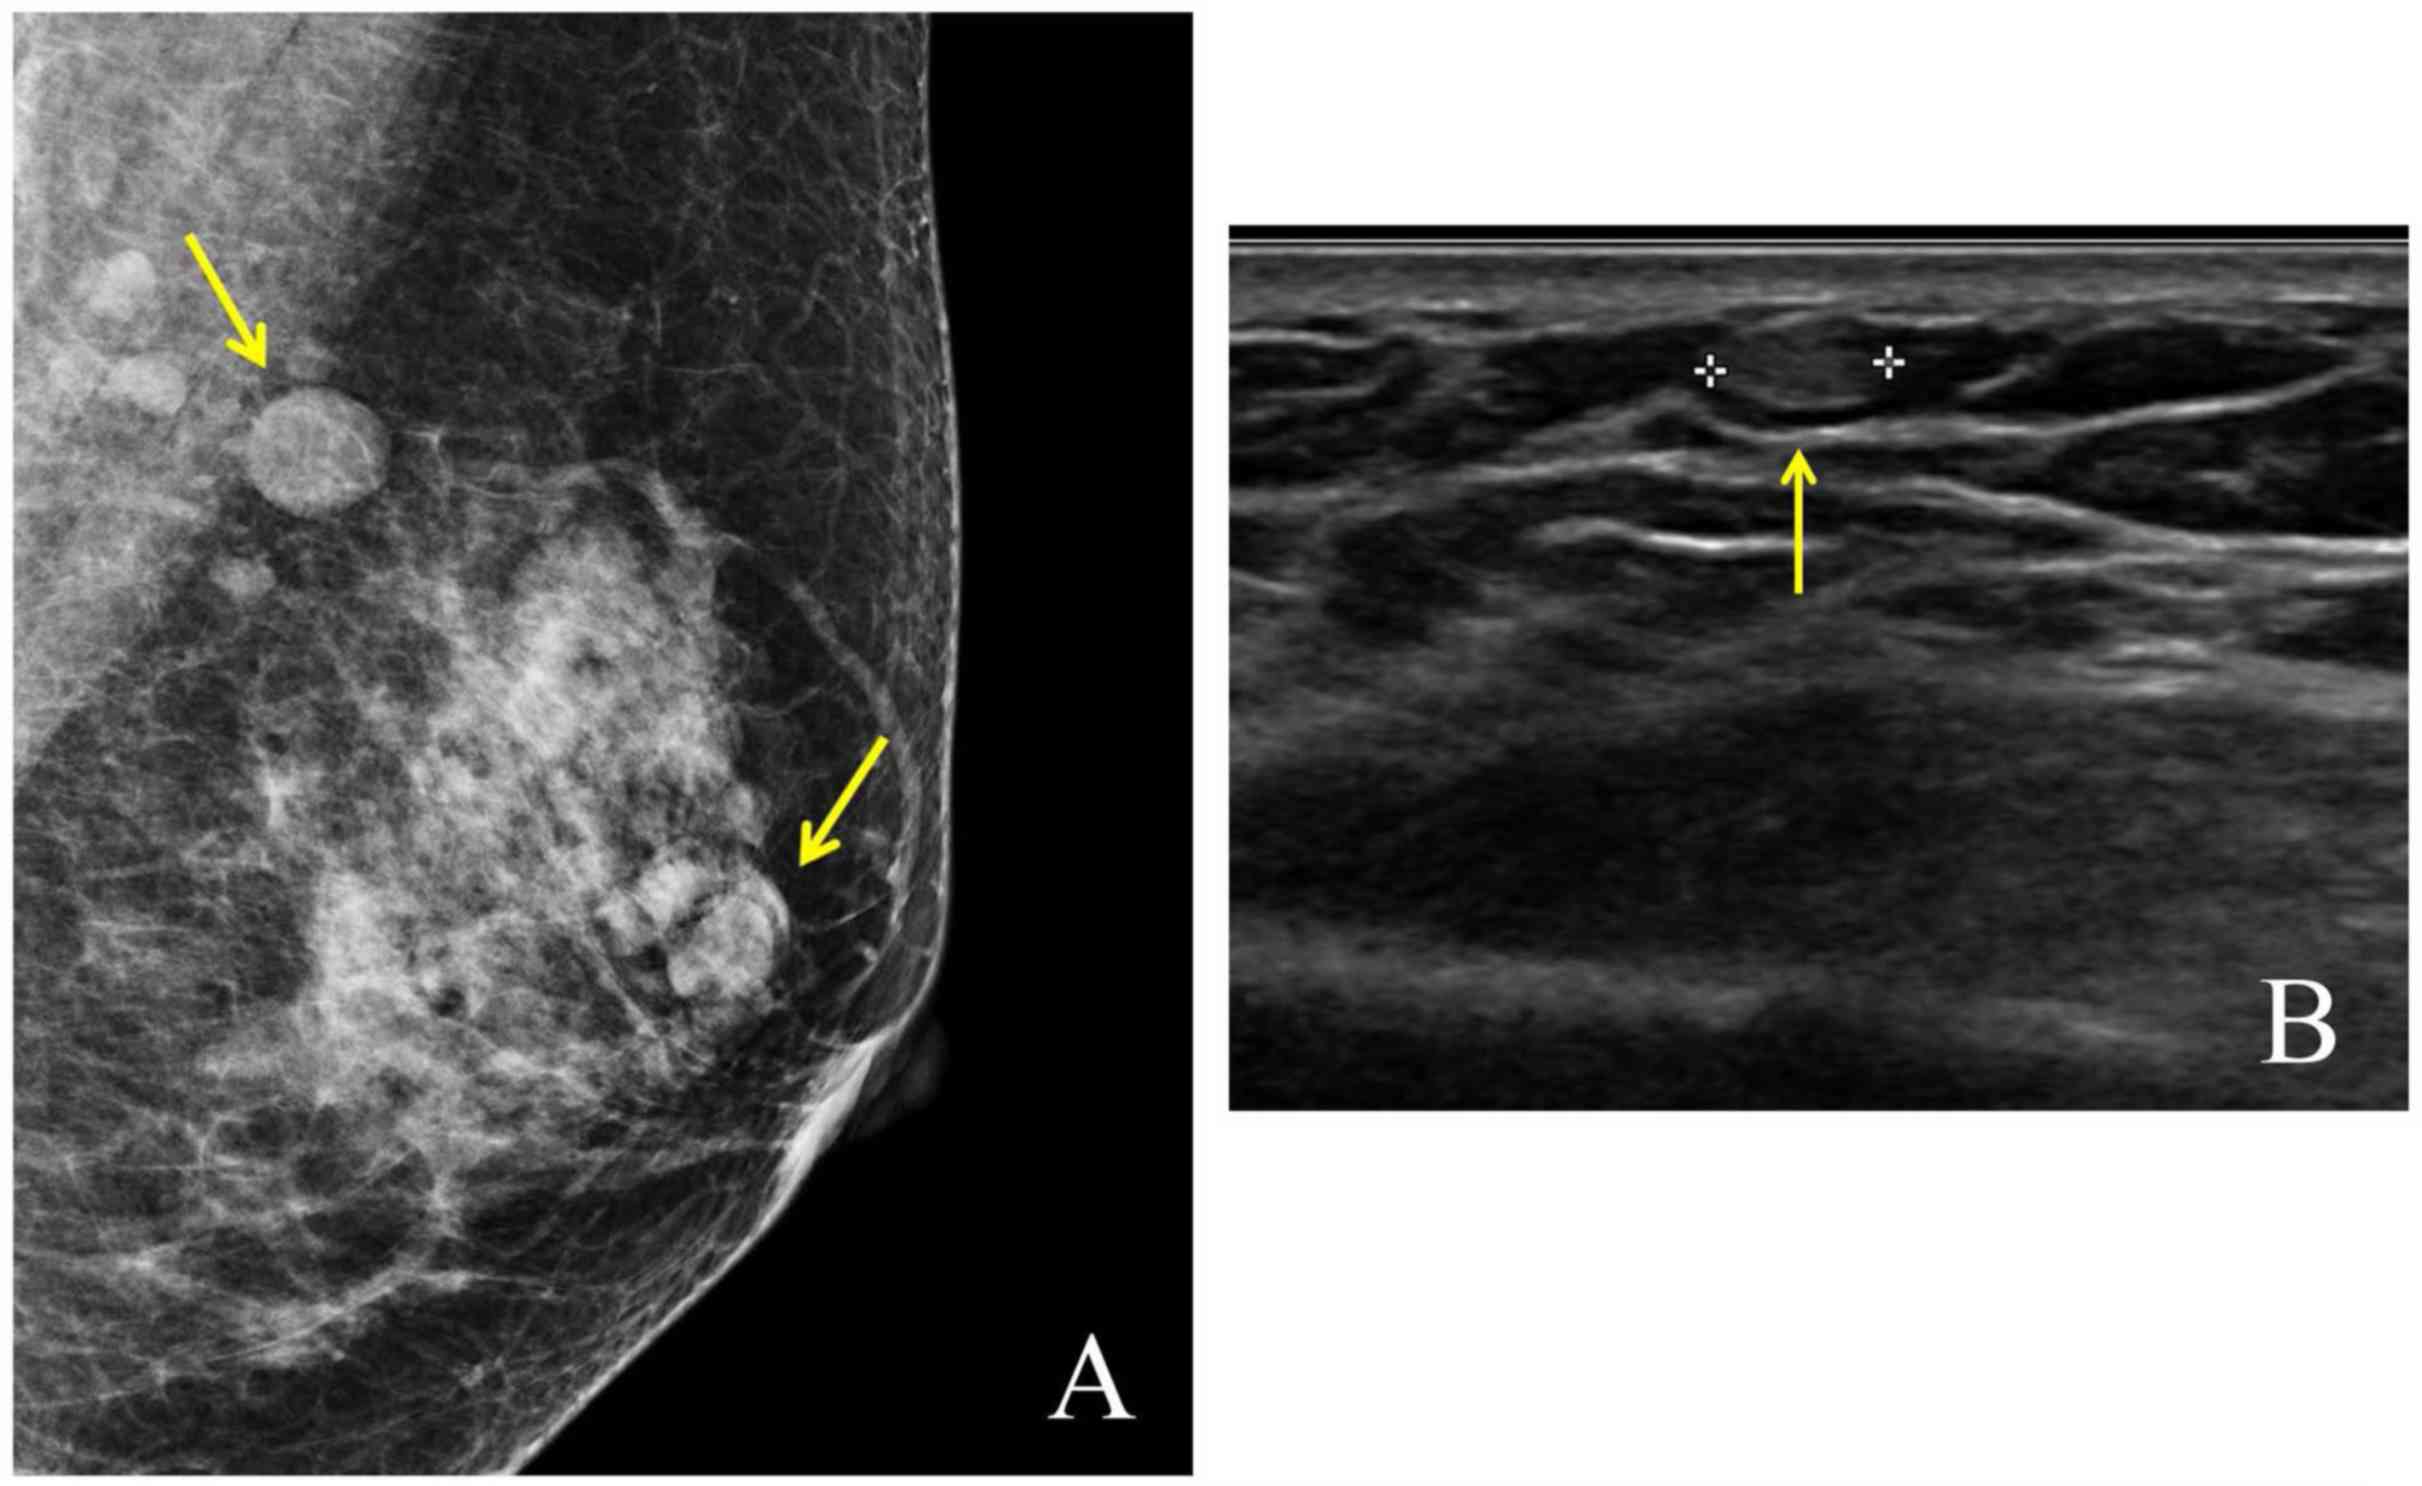

A 53-year-old woman was admitted to Kangbuk Samsung Hospital (Seoul, Korea) to confirm the breast lesion. She visited our Breast and Thyroid Center due to multiple nodular lesions in the left breast, which were detected during routine radiological examinations for more than 10 years. She has a surgical history of right thyroidectomy due to nodular hyperplasia diagnosed 16 years ago. In addition, she had excision for palpable masses in the right medial infraclavicular lesion (measuring 1.6 cm in the largest diameter) and left sternoclavicular junction (1.4 cm in the largest diameter) 10 years ago. The pathologic diagnosis for masses was ectopic thyroid. Thyroid function tests assessing TSH and Free T4 were carried out every year and showed euthyroidism status. Because the patient's thyroid function was normal, the patient did not receive any medications or thyroid hormone supplements, except vitamin D3. Ultrasonography performed 10 years ago showed multiple scattered cysts in bilateral breast. The largest lesion was located in the left breast and measured about 0.5 cm in size (Fig. 1). They were thought to be benign findings such as cysts, intra-mammary lymph nodes or fat necrosis based on Breast Imaging-Reporting and Data System 2 criteria. No associated inflammatory signs or skin changes were detected.

Figure 1.

(A) The mammography and (B) ultrasonography of patient shows multiple well demarcated nodules in left breast (arrows). Radiologist reported this lesion as Breast Imaging-Reporting and Data System 2.